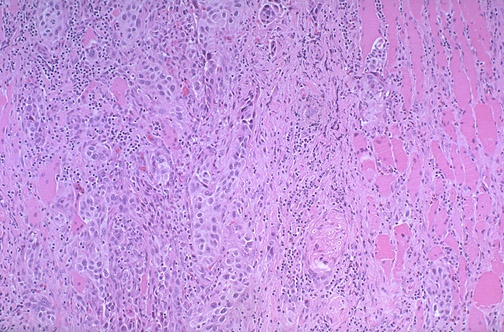

The anaplastic carcinoma shown here is invading into skeletal muscle fibers at the right. This is the most aggressive thyroid cancer, and fortunately the least common form of thyroid cancer.